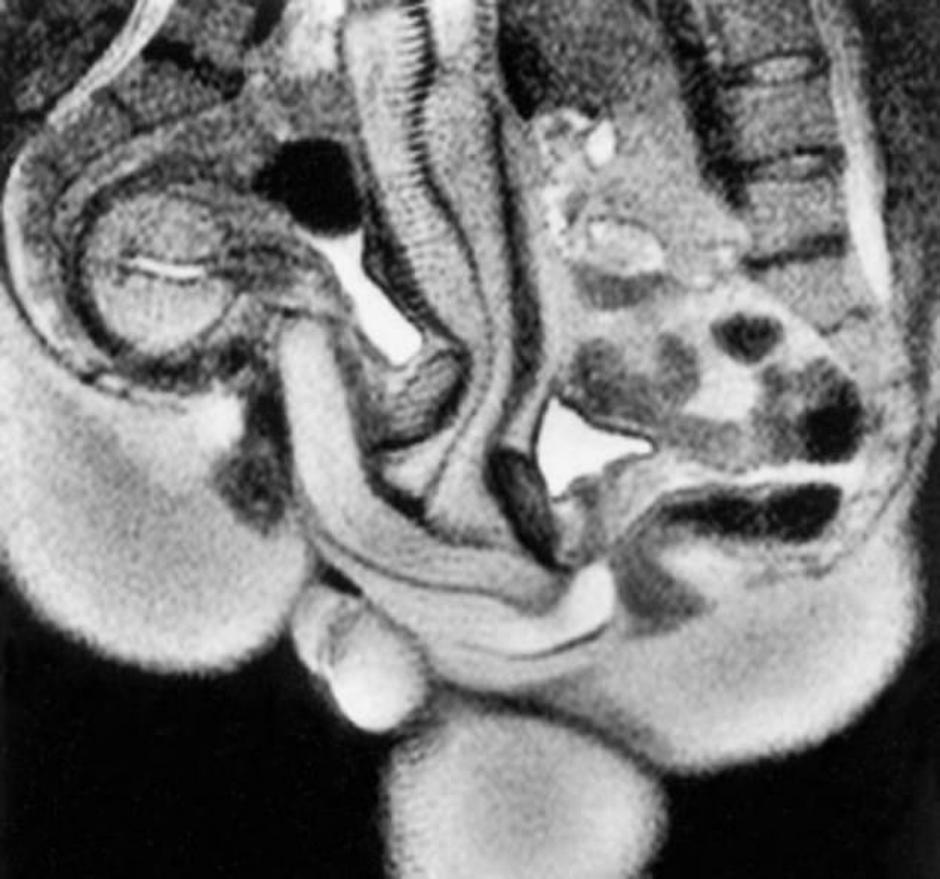

Britanski časopis British Medical Journal, to jest BMJ, objavio je prve MRI fotografije ljudi koji se seksaju, a i kažu kako su te fotografije popularne i 20 godina nakon objavljivanja. Fotografije su bile dio istraživanja, koje je promatralo parove kako se seksaju u raznim pozama, koje je objavljeno 1999. godine.

Glavno otkriće tog istraživanja je da penis poprima oblik bumeranga kada je u vagini, a do tada se mislilo da je ravan ili u obliku slova S.

Foto: BMJ